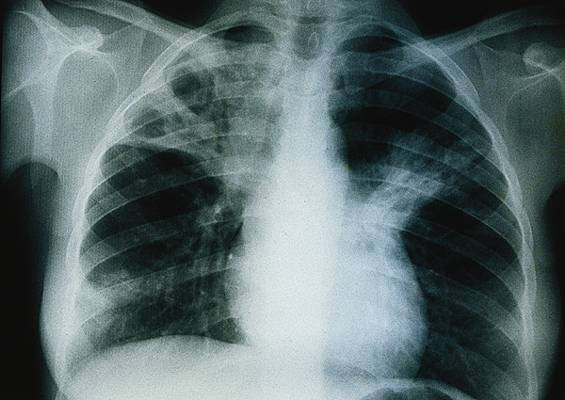

Voici la radiographie pulmonaire réalisée à l’entrée.

L’évolution n’est finalement pas en faveur d’une péricardite aiguë virale qui répond classiquement aux anti-inflammatoires. La persistance et l’aggravation de la symptomatologie doivent faire réévaluer l’importance de l’épanchement et doivent faire compléter le bilan étiologique.

Dans ce cas précis, nous apprenons que la patiente présente une symptomatologie respiratoire (toux, hémoptysies) s’aggravant depuis qu’elle est sous anti-inflammatoires, un syndrome fébrile persistant, une image radiologique excavée du lobe supérieur droit. Elle travaille au contact de réfugiés qui proviennent potentiellement de pays où la tuberculose est endémique. Il est donc légitime d’éliminer la tuberculose en première intention.

– bilan d’extension : radiographie pulmonaire, scanner thoracique.